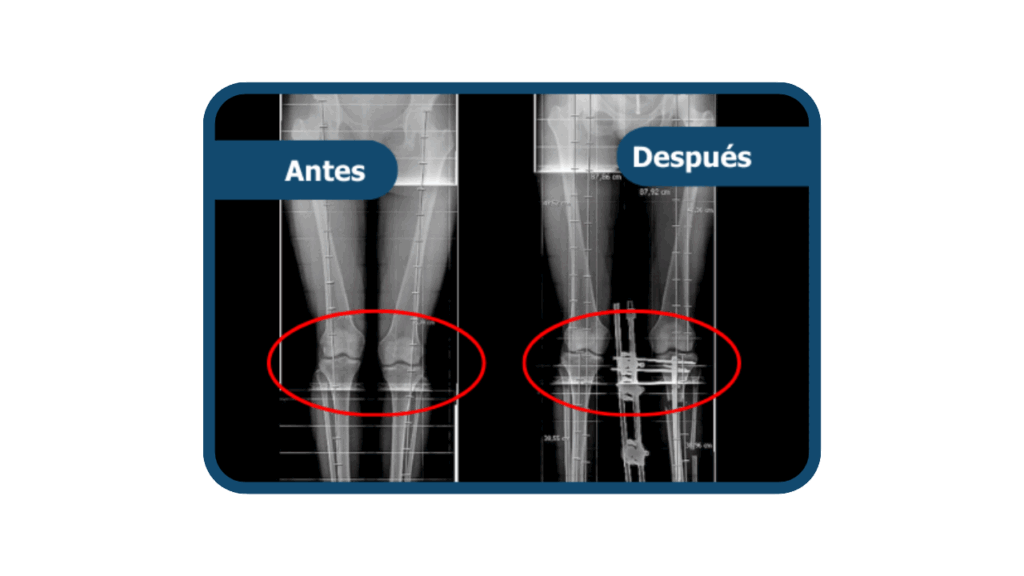

Genu valgo

Es una deformidad en la que las rodillas se desvían hacia adentro, generando una separación entre los tobillos y alterando la alineación de las piernas. Puede causar dolor, inestabilidad y desgaste articular. En Clínica Arthrosalud puede ser tratada por nuestros traumatólogos especialistas.

El tratamiento depende de la revisión profesional y el grado de la deformidad. En casos leves, se maneja con control médico y terapia física. En casos moderados o severos, se corrige mediante una osteotomía, cirugía que permite realinear el hueso y restaurar la correcta alineación de la pierna.